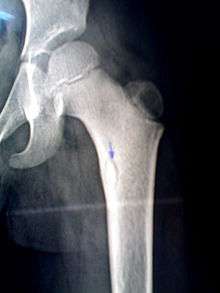

A sequestrum (plural: sequestra) is a piece of dead bone that has become separated during the process of necrosis from normal or sound bone.

It is a complication (sequela) of osteomyelitis. The pathological process is as follows:

The sequestra are surrounded by sclerotic bone which is relatively avascular (without a blood supply). Within the bone itself, the haversian canals become blocked with scar tissue, and the bone becomes surrounded by thickened periosteum.